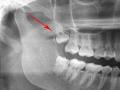

आरोग्य :चक्क दातांसह जबडाच काढून नव्याने बसविला; गंभीर म्युकरमायकोसिसचा परिणाम

६० रुग्णांवर शस्त्रक्रिया करून कोणाचा खालचा तर कोणाचा वरचा जबडा काढावा लागला. ...

नागपूर :म्युकरमायकोसिसनंतर पहिल्यांदाच जबडा व दंत प्रत्यारोपण

Nagpur News कोरोनातून बाहेर पडत नाही तोच ४३ वर्षीय रुग्णाला गंभीर स्वरुपाचा म्युकरमायकोसिस झाला. अशा स्थितीत शासकीय दंत महाविद्यालय व रुग्णालय त्यांच्या मदतीसाठी धावून आले. ...